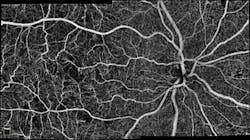

Optical coherence tomography (OCT) system maker Optovue (Fremont, CA) now offers higher-density OCT angiography (OCTA) imaging that improves resolution and peripheral visualization of vasculature in the eye. AngioVueHD Imaging provides OCTA scans with 73% more sampling points than the company's current AngioVue 6 × 6 mm scan, and improves image resolution by approximately 33% over the existing field of view. This enables physicians to more closely assess the fine vasculature in the eye for changes that could indicate ocular disease.

One of the major challenges of OCTA imaging is the limited region of the eye that can be visualized for assessing fine microvasculature. Currently, the standard field of view for the best image quality measures 3 × 3 mm. The feedback from early clinical evaluators of the AngioVueHD enhancements suggests the new 6 × 6 mm OCTA scan enables the improved likelihood of detecting abnormalities and assessing fine microvasculature details that would typically extend beyond the central 3 × 3 mm region.

The company also released AngioVueHD Montage, which automatically combines two high-density images—one at the central macular region (the portion of the retina responsible for central, high-resolution color vision that is possible in good light), and the other centered at the optic disc (the entry point for the major blood vessels that supply the retina)—in a 10 × 6 mm field of view. The ability to automatically create the montage is useful for imaging vasculature in potential pathologies that may extend into the periphery of the imaging plane.